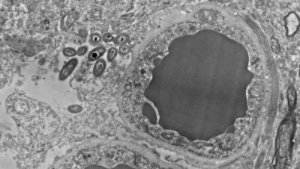

Tohtori Rosalinda Roberts ja hänen tiiminsä Alabaman yliopiston psykiatrian ja käyttäytymiseen perustuvan neurobiologian osastolta ovat vastuussa tästä löydöksestä. He tutkivat 34 ihmisen aivoja. Puolet aivoista oli terveitä ja toinen puoli kärsi skitsofreniasta. Lisäksi he tekivät rinnakkaisen tutkimuksen hiirien kanssa sulkeakseen pois sen vaihtoehdon, että bakteereita esiintyy vain kuoleman jälkeen tai että tutkimuksissa oli saastumisen aiheuttamia virheitä.

Molemmissa tutkimuksissa tutkijat havaitsivat bakteerien olemassaolon ihmisten ja hiirten aivoissa ei-tarttuvissa tai traumaattisissa tilanteissa. Itse asiassa he löysivät niitä useilla aivojen alueilla. Pääosin mustatumakkeessa, hippokampuksessa sekä etuaivolohkossa. Missään heidän tutkimissaan aivoissa ei myöskään ilmennyt tulehdusta.

Kuvat Rosalinda Robertsin, Courtney Walkerin ja Charlene Farmerin käyttöön luovuttamia.